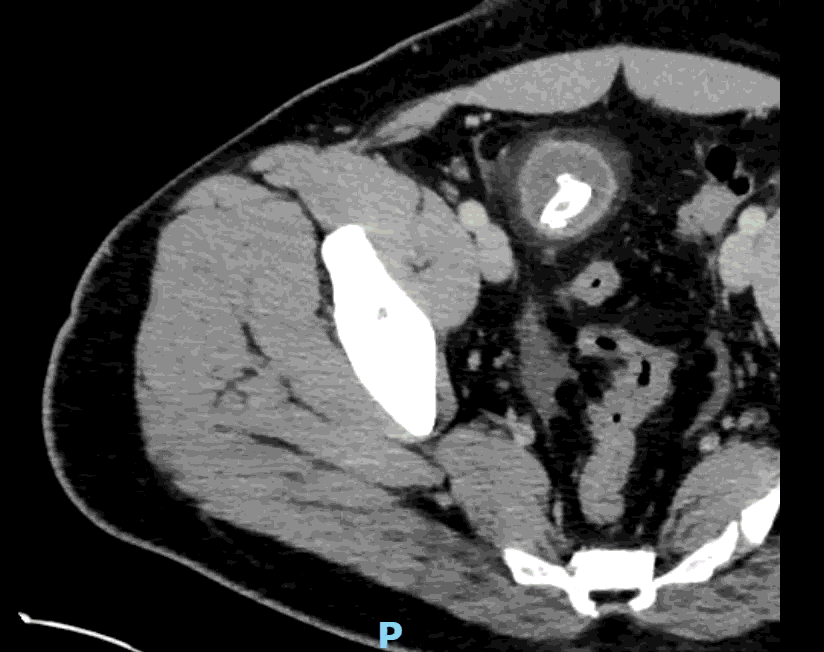

CT impression :

Right lower quadrant mid ileum 5.4 x 3.5 x 3.3 cm diverticulum, which may represent Meckel's diverticulum, containing calcifications/stones. Surrounding inflammatory fat infiltration suggesting Meckel's diverticulitis. Proximal small bowel distention with air-fluid levels, which may represent ileus versus partial small bowel obstruction. Unremarkable appearing appendix.